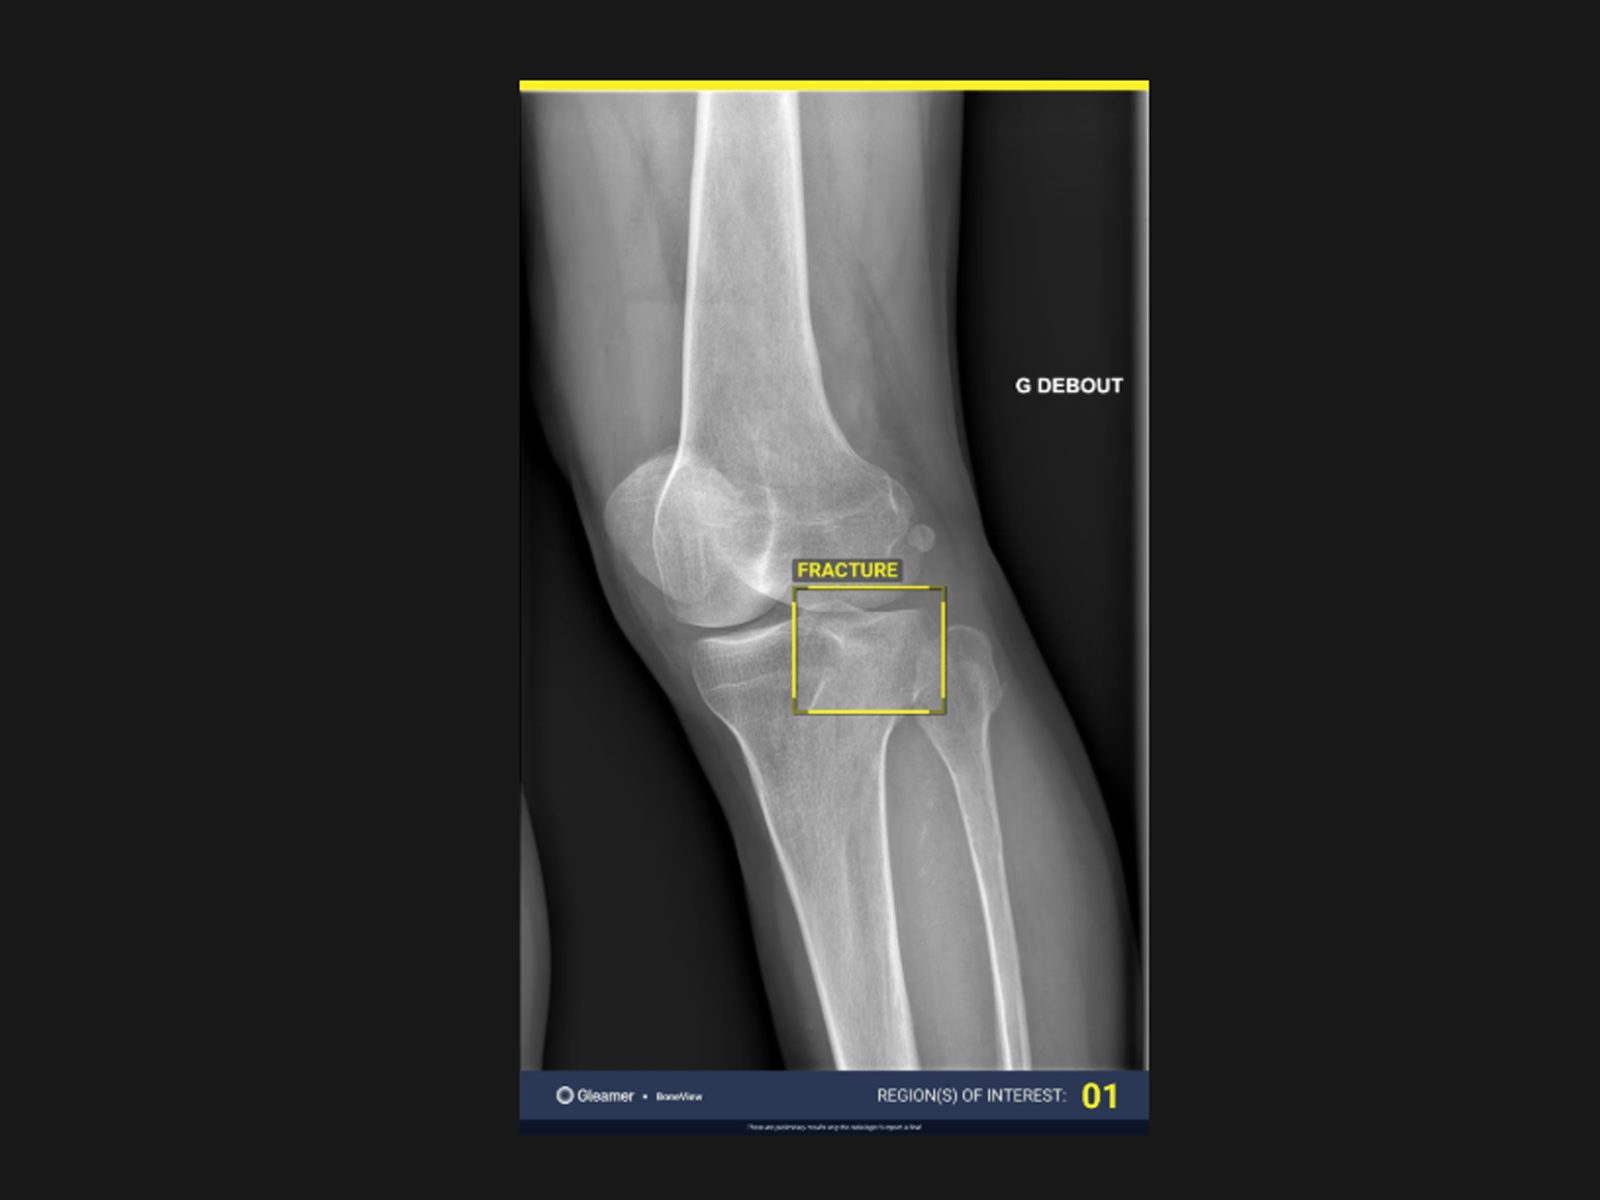

BoneView este o soluție de inteligență artificială care analizează radiografiile pentru a detecta automat fracturi și alte leziuni osoase. Aplicația examinează imaginile în câteva secunde și evidențiază zonele suspecte direct în PACS, ajutând medicii să identifice rapid patologia care poate fi omisă în citirea manuală.

Rezultatul este primit direct in viewer PACS si contine

• Contur „bounding-box” ce evidentiaza locatia patologiei detectate

• Numar al ariilor de interes